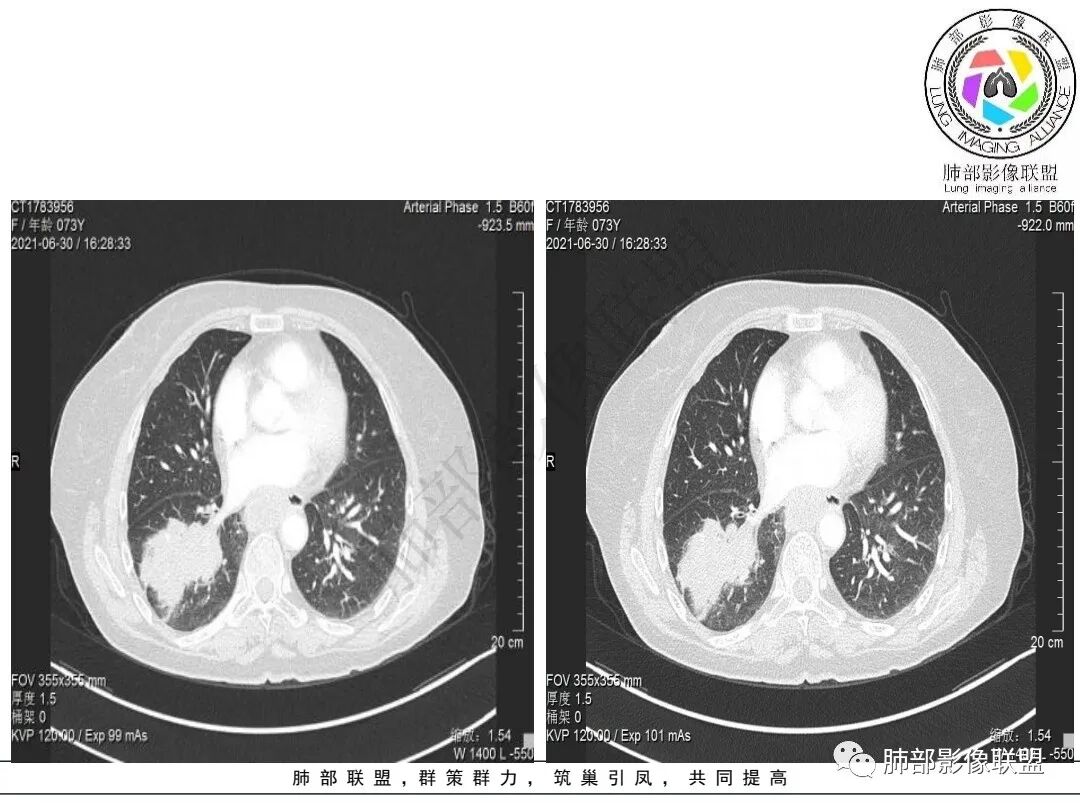

2.右肺下叶不规则实性密度块影,占据外后基底段及背段较大范围,可见轻度分叶、毛刺及棘状突起,未见明显胸膜牵拉及凹陷。

3.右肺下叶支气管轻度狭窄,病灶内见部分充气支气管征,外后基底段不能连续跟踪。

轻度不均匀强化,病灶内小血管显示不满意,未见明确坏死区。

4.右肺门及纵隔见多处增大淋巴结,不均匀环形强化,后下纵隔(隆突下)肿大淋巴结十分显眼!